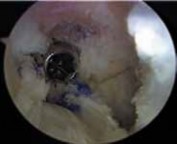

5. In revision ACL reconstruction, the notch often is overgrown and narrow, likely as a result of the previous ACL reconstruction (

TECH FIG 1A

).

1. A notchplasty is completed with use of a 5.5-mm burr, starting at the anterior opening of the notch if necessary.

2. The location of the previous femoral tunnel is noted.

3. Notchplasty is carried back to the posterior wall as needed. A small, curved curette may be used to inspect the back of the notch. A thin white strip of periosteum usually identifies the posterior wall (

TECH

### FIG 1B). Careful attention to localizing the posterior wall is critical, especially because the sides and roof of the notch often are irregular owing to the previous surgery.

1. Anterior placement of the femoral tunnel is the primary cause of recurrent laxity for ACL reconstructions, so in many cases there is enough room to place a second femoral tunnel in the appropriate position without interference or compromise from the previous tunnel. If this is the case, the previous interference screw can be left in place or removed (

TECH FIG 1C,D

TECH FIG 1 • A. Significant overgrowth of the notch noted at the time of revision anterior cruciate ligament (ACL) reconstruction. B. A thin layer of periosteum is easily visualized at the posterior wall of the notch. C. Note the anterior placement of the femoral tunnel interference screw used during the primary ACL reconstruction. The femoral tunnel for the revision can be placed at the appropriate location without removing the interference screw used in the primary procedure. D. The new femoral tunnel and interference screw are placed in the appropriate location without compromise from the screw used in the index procedure. E. View of femoral notch after placement of femoral tunnel and interference screw via anteromedial portal. This allows divergence of the old and new femoral tunnels.